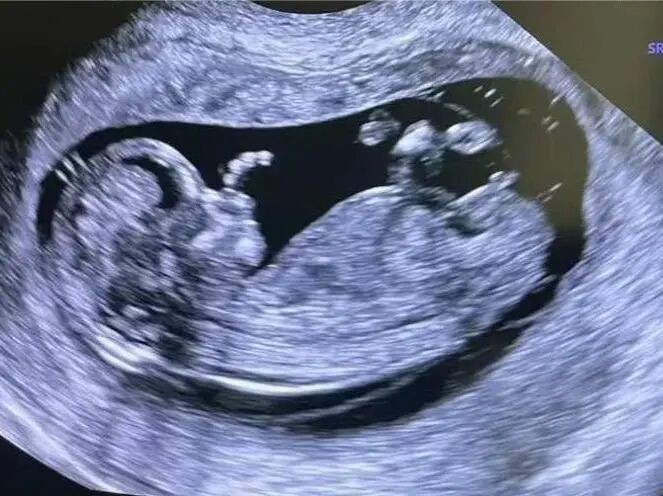

4月2日,贵州航天医院第55次晨读会由我院超声科医师敖春庆作学术交流,她以“中孕期产前超声筛查技术”为题,详细讲解了进修学习的成果,分享了科室实际开展的病例,阐述了未来的工作计划与展望,并结合典型病例图文分析等形式,强调了中孕期产前超声筛查的重要意义。 超声科专家简介 吴艳辉 中共党员,超声科学科带头人、主任,主任医师 临床擅长:从事超声诊断工作约30年,对心血管、小器官超声、超声引导下介入等具有丰富的临床经验。 骆科美 中共党员,超声科副主任医师 临床擅长:从事超声诊断工作33年,对胎儿心脏及颅脑、妇产超声、盆底超声等诊断具有丰富的临床经验。 胡大海 超声科副主任医师 临床擅长:从事超声工作17年,对心血管、外周血管、浅表器官超声诊断等具有丰富的临床经验。 刘 敏 超声科副主任医师 临床擅长:从事超声诊断工作20余年,对妇产科超声、心脏血管超声诊断具有丰富的临床经验。 敖春庆 超声科主治医师 临床擅长:对腹部、泌尿、妇科等超声诊断具有丰富的临床经验。 超声科简介 基本情况 贵州航天医院超声科配备多种超声检查设备(飞利浦彩超(IU-22、IU-Elite、HD11、Q5、Q7),迈瑞超声I9、DC-6、DC-8、GE-E8及床旁机,彩色超声诊断仪等),设有心血管诊室、妇产科诊室、腹部诊室、浅表小器官等检查室。 专科特色 四肢血管超声检查、双胎产前筛查及超声监护、超声造影检查技术、介入超声临床应用、经颅脑实质超声辅助筛查诊断帕金森病、女性性早熟超声诊断、盆底超声检查等。 NT超声检查 超声介入引导 肝脏超声造影 甲状腺造影 颅脑超声帕金森辅助检查 乳腺超声造影 上肢动静脉造瘘超声检查 双胎超声筛查 下肢血管超声检查 右心造影 诊疗范围 科室业务覆盖腹部、泌尿、妇科、产科(常规、NT筛查、III级筛查超声检查及高危妊娠监护)、成人心脏、外周血管、浅表器官(包含甲状腺、乳腺、阴囊、眼睛等)、颅脑(小儿颅脑、成人颅脑)、小儿肺超、造影、盆底、腹直肌、肌骨神经等检查及各种介入引导。 end